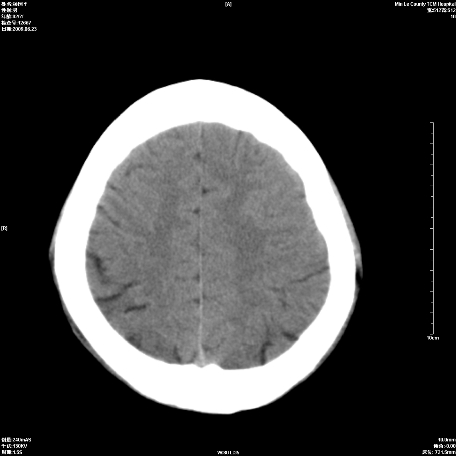

以下是引用随光逐影在2009-6-23 14:30:00的发言:[br]1)颅脑ct轴位平扫颅内未见明确异常。2)左侧额部头皮软组织肿胀。[br][br](双侧苍白球见对称性钙斑,透明隔间腔与vergae腔并存)